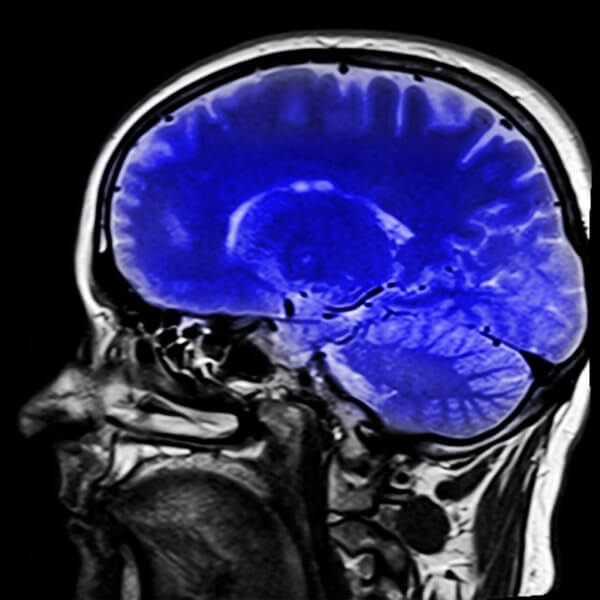

ですので、医師がこの病気の診断に役立てることのできる神経のテストがあります。MRIはどんな種類の梗塞が起こったのかを特定してくれるので、病状を見極める助けになります。